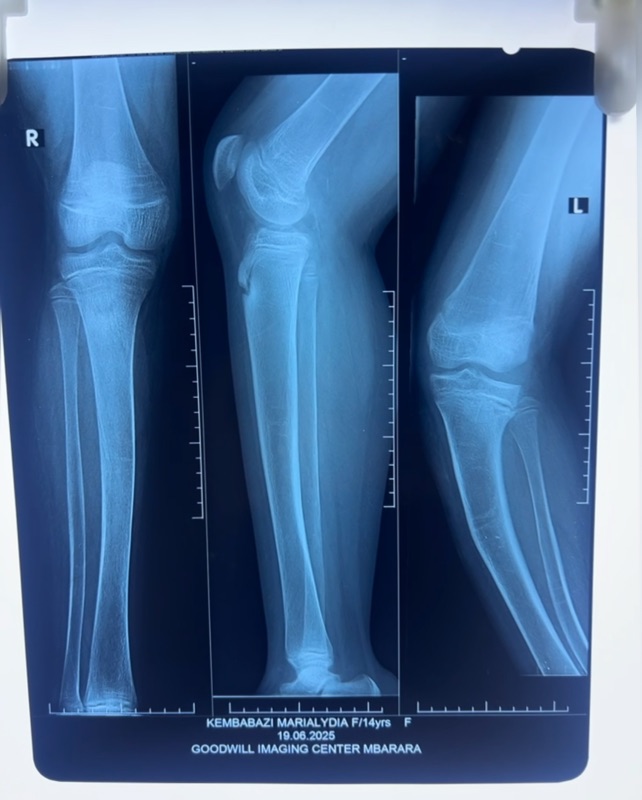

- Este mes se han realizado 4 operaciones una de ellas para retirar un tumor cancerígeno a Cecilia. También han sido operados Joseph, Darius y Lydia. El precio de las 4 operaciones ha sido de 431€.